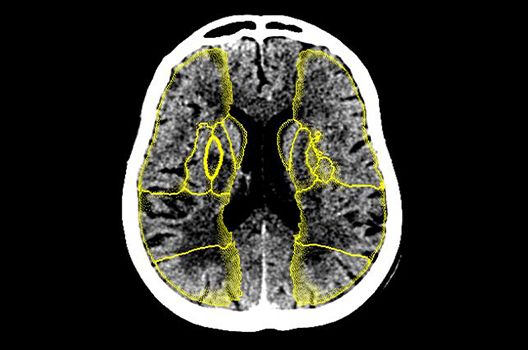

Die Schwerpunkte in der CT-Forschung liegen in der Bildnachverarbeitung, der Dosis- und Artefaktreduktion sowie der quantitativen und automatisierten CT-Bildanalyse.

Die Computertomographie (CT) ist ein Verfahren, bei der mit Hilfe von Röntgenstrahlung Schnittbilder des Körperinneren angefertigt werden. Unser Bestreben ist es hierbei, bei möglichst niedriger Strahlendosis eine bestmögliche Bildqualität zu erzielen. Eine zunehmend große Rolle in der radiologischen Forschung spielen zudem die Automatisierung in der Bildanalyse und die computergestützte Auswertung großer Datenmengen, wie sie bei einer CT-Untersuchung anfallen. Wir arbeiten in enger Kooperation mit den Geräteherstellern zusammen und sind daher maßgeblich an der Entwicklung und Erprobung neuer Techniken beteiligt.